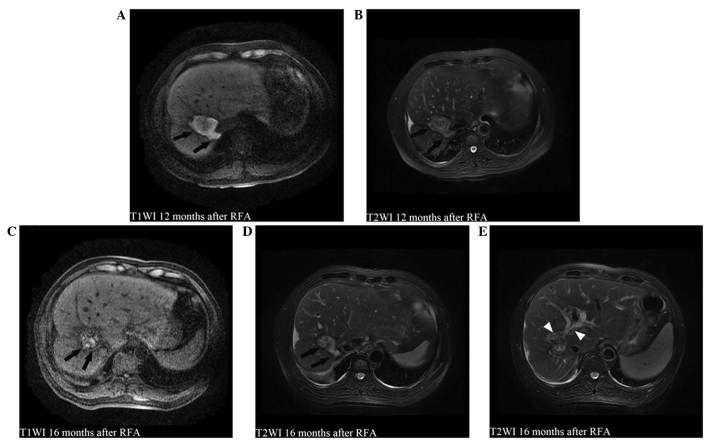

Figure 4.

MRI scans at 12 and 16 months after RFA showing (A-E) a biloma at the ablation zone (black arrows) and an increase in bile leakage compared with the MRI scans performed at 1 month after RFA (Fig. 2). (C-E) The biliary sludge and stones in the biloma and dilated bile duct were also detected on MRI scans at 16 months after RFA (white arrowheads). MRI, magnetic resonance imaging; RFA, radiofrequency ablation; T1WI, T1-weighted imaging; T2WI, T2-weighted imaging.

The damage to the diaphragm and the formation of a biloma may be predominantly attributed to the thermal effects of RFA on the diaphragm and bile duct. A large tumor, close to the hilum or hepatic dome, has been found to be a predisposing factor of BBF following RFA (8,11). In the present case, a liver tumor measuring 44×34 mm, which was located near the right hepatic bile duct and dome, was treated with RFA, and the ablation zone was found to have reached a size of 75×54 mm on MRI at 1 month after RFA. The ablation zone margin was found to reach the diaphragm and a small amount of right pleural effusion was observed on the MRI scan (Fig. 2), suggesting the possibility of diaphragmatic injury. Although no active biliary fistula leak was directly detected by MRI scan at 1 month after RFA, bile leakage was observed (Fig. 2). The hepatectomy performed later also confirmed that the biliary fistula originated from the right hepatic bile duct, which directly communicated with the biloma. In addition, the bile duct obstruction, which had been caused by a large volume of biliary sludge and stones, could have contributed to the rising pressure of the biloma and its later rupture, as the increase in bile leakage, biliary sludge and stones and bile duct dilation (Fig. 4) were detected on the follow-up MRI scan prior to the rupture of the biloma. The existence of a biloma might have also caused the repeated biliary infection, which was responsible for the fever that persisted even after percutaneous biloma drainage was performed; therefore, in the present case, various pathological conditions could have simultaneously contributed to the formation of a delayed BBF.

Had the biloma and its enlargement been identified early on, during the follow-up MRI scan, and the percutaneous biloma drainage been performed in a timely manner, the development of BBF and subsequent surgical intervention could have been prevented. In fact, the biloma was present 1–16 months after RFA, before the patient presented with fever and coughing up of bile-tinged sputum. The biloma was retrospectively observed on a review of the MRI scan performed 1 month after RFA (Fig. 2). In addition, on the follow-up MRI scans at 3, 6, 12 and 16 months after RFA, biloma enlargement, bile duct obstruction, caused by a large volume of biliary sludge and stones, and bile duct dilation were detected (Fig. 4). The bile duct obstruction led to an increase in the bile leakage and pressure of the biloma, prior to the rupture of the biloma. These results were supported by the hepatolobectomy that was later performed. The findings of the present study suggested that, when biloma enlargement is observed on follow-up MRI scans, timely percutaneous biloma drainage should be performed to prevent its rupture and the development of BBF.